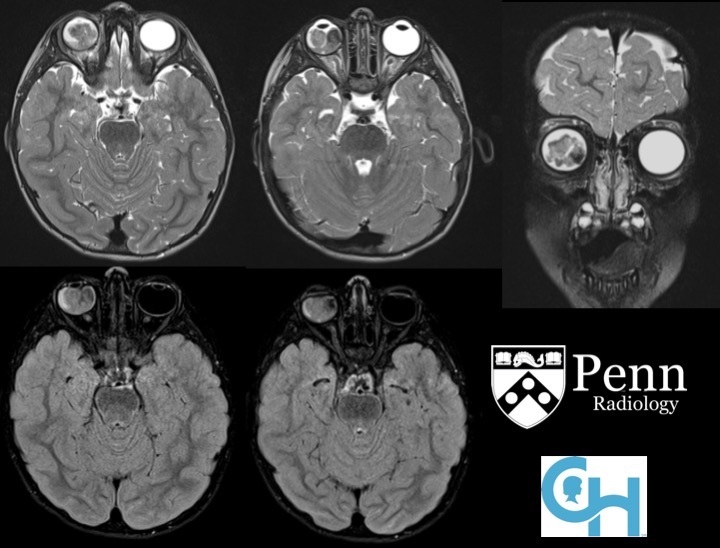

There is a lobulated mass within the right globe that is T1-hyperintense and heterogeneously T2-hypointense relative to vitreous fluid, and which displays restricted diffusion and contrast enhancement. There is retinal detachment with associated hemorrhage, resulting in a fluid/fluid level in the right globe seen on the T2-weighted images.

Retinoblastoma is the most common intraocular childhood malignancy, with a median presentation of 12 months. It can be sporadic (approximately 60% of cases), which requires two spontaneous mutations of the retinoblastoma protein tumor suppressor gene (RB), or it can be familial, due to a single spontaneous mutation in combination with an inherited germline mutation.

Retinoblastomas appear as mixed calcified and noncalcified soft-tissue intraocular masses. CT and ultrasound are good for depicting intralesional calcifications. On MRI, they will appear as a T1-hyperintense, T2-hypointense mass relative to vitreous fluid. Retinoblastomas will restrict on diffusion imaging given that they have a high cellular content as they fall within the class of small blue round cell tumors. The contralateral globe, pineal region, and suprasellar regions need to be carefully evaluated for the presence of additional sites of disease.